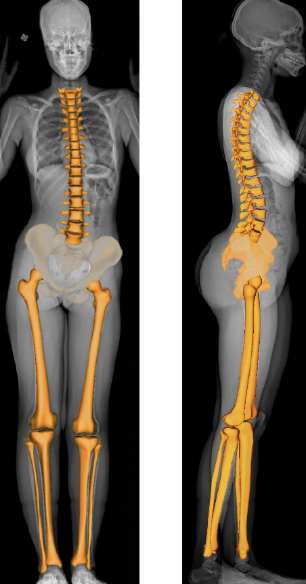

Imagerie : standard pour quantifier l’anatomique

Radiographie plein membre debout en charge

EOS

En pratique en France, EOS est privilégiée quand disponible (dose plus faible), mais la télémétrie plein membre debout reste largement utilisée

Avantages de l’EOS:

• mesure en charge

• faible irradiation comparée aux radiographies conventionnelles

• excellente reproductibilité

Corrélation élevée avec les techniques historiques de référence (scanogramme).

(Sabharwal 2006 ; Alfuth 2021)

C’est la méthode de référence pour quantifier une ILMI anatomique.

La télémétrie classique (radiographie plein membre debout)

Avant la diffusion du système EOS, la télémétrie plein membre debout en charge était la méthode standard pour évaluer une inégalité de longueur des membres inférieurs.

Elle reste aujourd’hui très répandue en France.

Principe

• Radiographie antéro-postérieure (AP) des deux membres inférieurs

• Patient debout, en charge bipodale

• Mesure de la distance entre repères osseux (tête fémorale → interligne tibio-talienne ou malléole)

Elle permet d’évaluer :

• longueur fémorale

• longueur tibiale

• ILMI totale

• alignement frontal (axe mécanique)